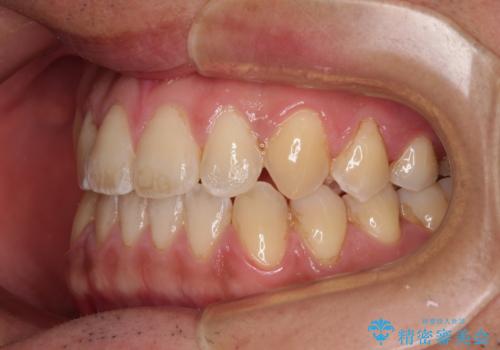

- 前歯のデコボコを気にして来院された患者様です。

歯列としてはワイヤー装置でもインビザラインでも対応可能でしたが、インビザラインが苦手とする上顎側切歯(真ん中から2番目の歯)の舌側転位が顕著でした。

治療の確実性を上げるために、インビザライン開始前に上顎のワイヤー装置にて舌側転位を解消し、その後インビザラインにて矯正治療を行うこととしました。

前歯のデコボコが早めに改善され、スムーズに治療を終えることができました。